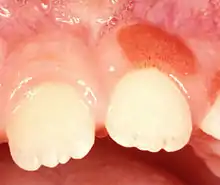

| Plasma cell gingivitis in an adult (histologically verified). |

Plasma cell gingivitis appears as mild gingival enlargement and may extend from the free marginal gingiva on to the attached gingiva.[6] Sometimes it is blended with a marginal, plaque induced gingivitis, or it does not involve the free marginal gingiva. It may also be found as a solitude red area within the attached gingiva (pictures). In some cases the healing of a plaque-induced gingivitis or a periodontitis resolves a plasma cell gingivitis situated a few mm from the earlier plaque-infected marginal gingiva. In case of one or few solitary areas of plasma cell gingivitis, no symptoms are reported from the patient. Most often solitary entities are therefore found by the dentist.[2]

The gums are red, friable, or sometimes granular, and sometimes bleed easily if traumatised.[6] The normal stippling is lost.[7] There is not usually any loss of periodontal attachment.[6] In a few cases a sore mouth can develop, and if so pain is sometimes made worse by toothpastes, or hot or spicy food.[7] The lesions can extend to involve the palate.[7]